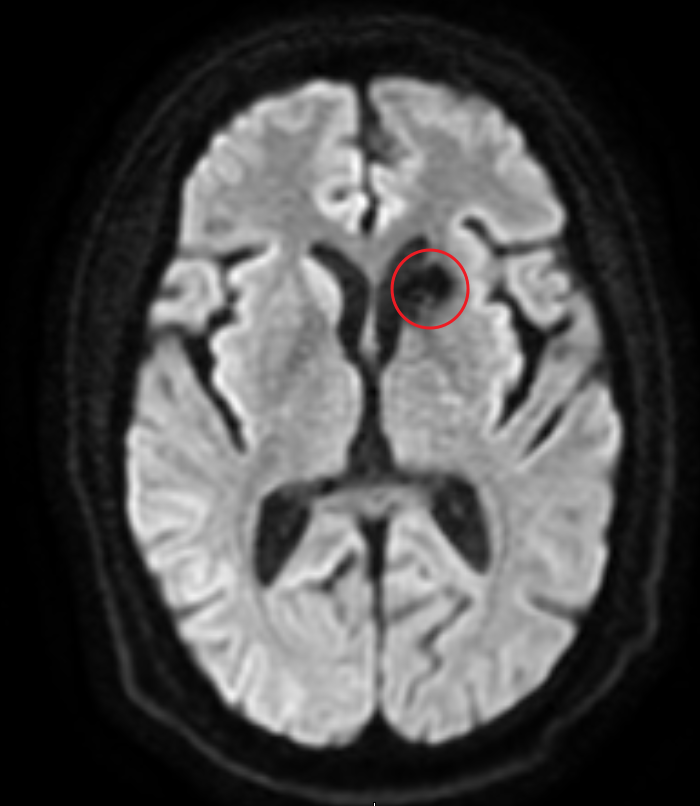

MR. Magnetic Resonance. En billeddannelsesteknik, hvor man lægges i et meget kraftigt statisk magnetfelt så alle protoner orienterer sig på langs med magnetfeltet. Man exciterer dem så med et radiofelt på tværs af det statiske magnetfelt, og måler på de radiobølger protonerne udsender, når der slukkes for radiofeltet og de returnerer fra deres resonans til at spinne omkring det statiske felt. Find ud af mere på Danish Research Center for Magnetic Resconance.

Der findes langt flest protoner i det vand, der er overalt i kroppen. Naboprotoner påvirker hinanden, og derfor bliver radiosignalet fra protonernes resonans forskelligt afhængig af densiteten af det væv, de er i. Skanneren laver forskellige sekvenser af billeder. Sekvenserne defineres af måleparametre, som f.eks. ventetid mellem excitation og måling. Det fremhæver forskellige vævstyper. Der kan også injiceres kontrastvæske undervejs, igen for at få bestemte vævstyper til at blive tydeligere.